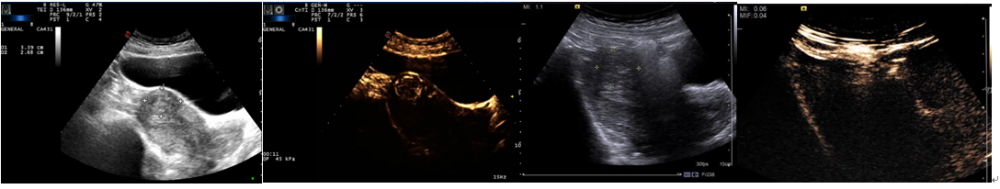

案例9:林**,女,53岁,发现子宫肌瘤5年余,痛经1月,B超提示子宫底部见一低回声团大小59*52mm,超声介入下活检提示“子宫”平滑肌瘤,灶区细胞较丰富,在全麻+局麻后,实时超声择点定位及引导下行穿刺活检术+子宫肌瘤射频消融术,术中即时超声造影提示子宫肌瘤消融后无增强区范围约50*33mm;术后3月门诊复查无诉不适,超声造影提示子宫肌瘤消融后无增强区范围约49*32mm。